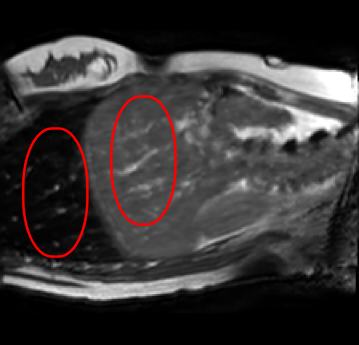

Qualitative results are shown in Fig. 4. We observe no large qualitative differences in the performances of MFIN and MFINc for either loss function. Since, MFINc-SSIM provides the best quantitative results, we show interpolated images from this method and compare them against SCIN-SSIM. Both methods perform well when the motion between the neighbouring images is low. This is reflected in the absence of any structures in the error images in Fig. 4.1. However, RMSE is lower for SCIN because it produces a denoised interpolated image, while MFIN carries over the noise pattern from the neighbouring known image. Whenever there exists high motion between the images being interpolated, SCIN produces blurry images and often misses image structures. This can be observed in cases 2-4 in Fig. 4. For all these cases, MFINc (and also MFIN) produces sharp images and largely preserves structures in the images. Fig. 4.2 shows a case where MFINc additionally has a much better performance with respect to image alignment. Fig. 4.3 shows a representative case, with small improvement in image alignment, yet worse RMSE and SSIM values for MFINc. Finally, Fig. 4.4 shows a case, where MFINc produces worse alignment of structures than SCIN.

1)

14.13, 0.81 13.02, 0.84

2)

9.16, 0.76 10.12, 0.74

3)

9.75, 0.85 12.94, 0.81

4)

a b c d e